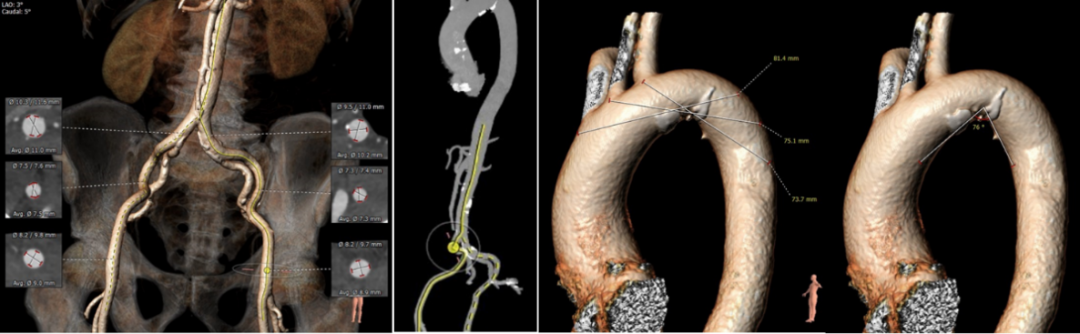

▪ 入路血管散在钙化,局部较严重,双侧血管内径良好,整体入路血管条件良好。

外周血管入路评估